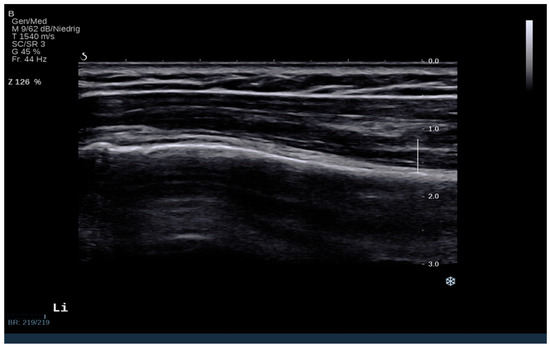

Deltoid Muscle Tension Alterations Post Reverse Shoulder Arthroplasty: An Investigation Using Shear Wave Elastography

2. Materials and Methods